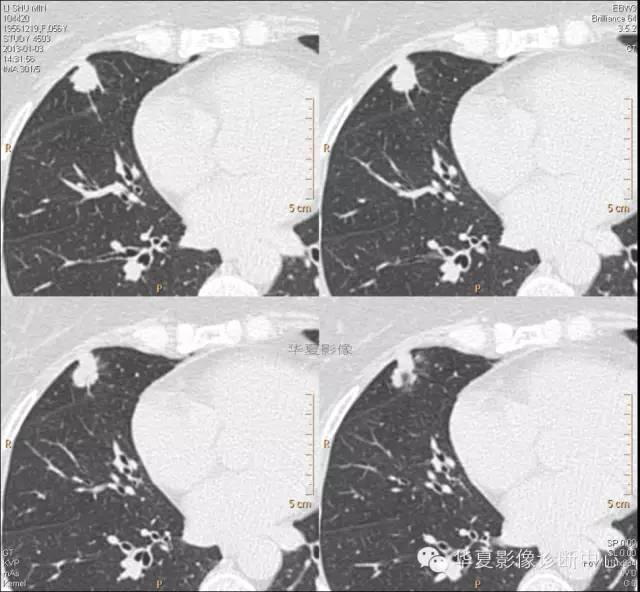

【病例学习】典型周围型肺癌CT病例一例

女,56岁,其父因肺癌去世,自觉胸部疼痛不适来诊要求拍胸片。